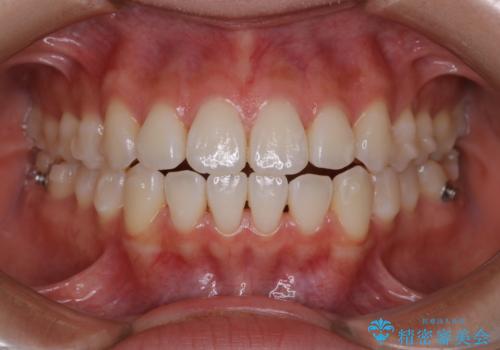

前歯で噛めない:オープンバイト(開咬)を非抜歯インビザラインで治療

舌癖も認められたため、舌のトレーニングも併せて行い、矯正治療の効率化を図ると同時に後戻りのリスクを最小限に抑えるようにしました。

オープンバイトの方への治療は、通常抜歯を行いワイヤーによる矯正治療を行うことが多いですが、今回はインビザラインの特性を生かし、非抜歯にて綺麗な歯並びを作ることが出来ました。

舌癖がある方は、歯を内側から押し出す力が日常的に働くため、矯正治療後も歯と歯の隙間が開いてしまうなどの後戻りのリスクが高いことが知られています。舌の正しいポジショニングやお口周りの筋肉のトレーニングを行うことで後戻りのリスクを減らすことが可能です。